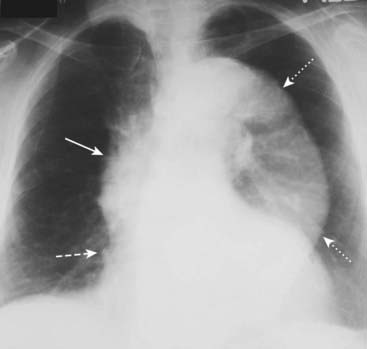

image

Figure 9-27 Aortic dissection.

Conventional radiographs are not sensitive enough to be diagnostically reliable for aortic dissection, but they may point to the diagnosis when several imaging findings are seen together, especially in the proper clinical setting. “Widening of the mediastinum” is frequently not present and is a poor means of establishing the diagnosis, although in this patient the mediastinum is clearly widened by an enlarged aorta (double black arrow). Also, a left pleural effusion is present (solid black arrow). The combination of a widened mediastinum and a left pleural effusion in a patient with chest pain should alert you to the possibility of an aortic dissection.

imageOn both MRI and CT, the diagnosis rests on identification of the intimal flap that separates the true (original) from the false lumen (canal created by the dissection) (Fig. 9-28).

Figure 9-28 Aortic dissections, types A and B.

A, An intimal flap is seen to traverse both the ascending (solid black arrow) and descending aorta (dotted black arrow). This is a Stanford type A dissection. B, There is a normal-appearing ascending aorta (dotted white arrow) while an intimal flap is noted by the black line traversing the descending aorta (solid black arrow). The intimal flap is the characteristic lesion of an aortic dissection. The smaller lumen is usually the true (original) lumen, and the larger, false lumen is actually a channel that has been produced by blood dissecting through the media.